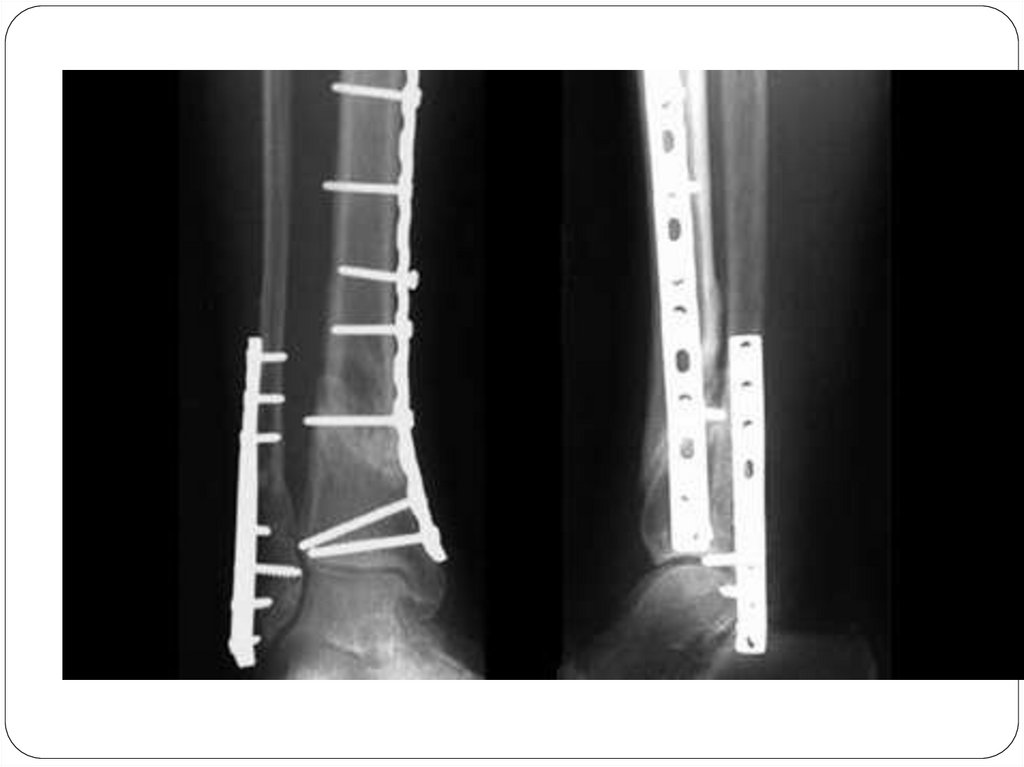

ОПЕРАТИВНОЕ ЛЕЧЕНИЕ ПЕРЕЛОМОВ

Оперативное лечение перелома

предусматривает одномоментную

открытую (чаще) или закрытую (реже)

репозицию костных отломков и их

прочную фиксацию – остеосинтез.

Различают 2 основных вида

остеосинтеза:

внутренний (погружной) с

помощью спиц, винтов,

штивтов.

наружный – аппаратами

внешней фиксации (аппарат

Илизарова)

Накостный остеосинтез – фиксация отломков

осуществляется при помощи пластины,

закрепляемой винтами на поверхности кости.